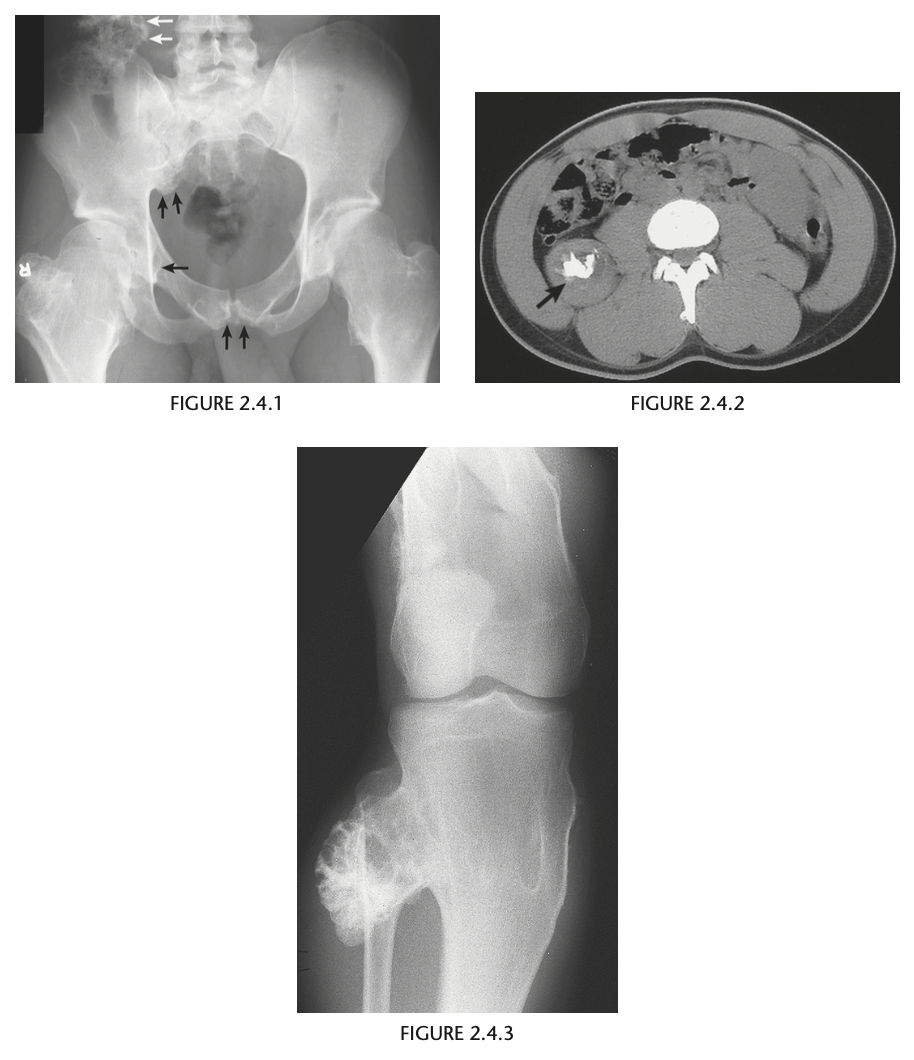

23 year old man with pain in the right hip

An anteroposterior view of the pelvis

shows flaring of the metaphyseal regions of

the proximal femurs and numerous osteochondromas

arising from the right iliac crest, pubic bones, and proximal right femur (arrows).

Axial CT through upper pelvis - Large right exostosis with soft tissue mass.

AP radiograph of knee - multiple osteochondromas arising from femur and fibula.

DIAGNOSIS: Multiple hereditary exostosis

AD disorder age 10-20s

Signs of malignant transformation - Growth of previous stable exostosis, new or increasing calcifications, new bony erosion

Associated with chondrosarcoma